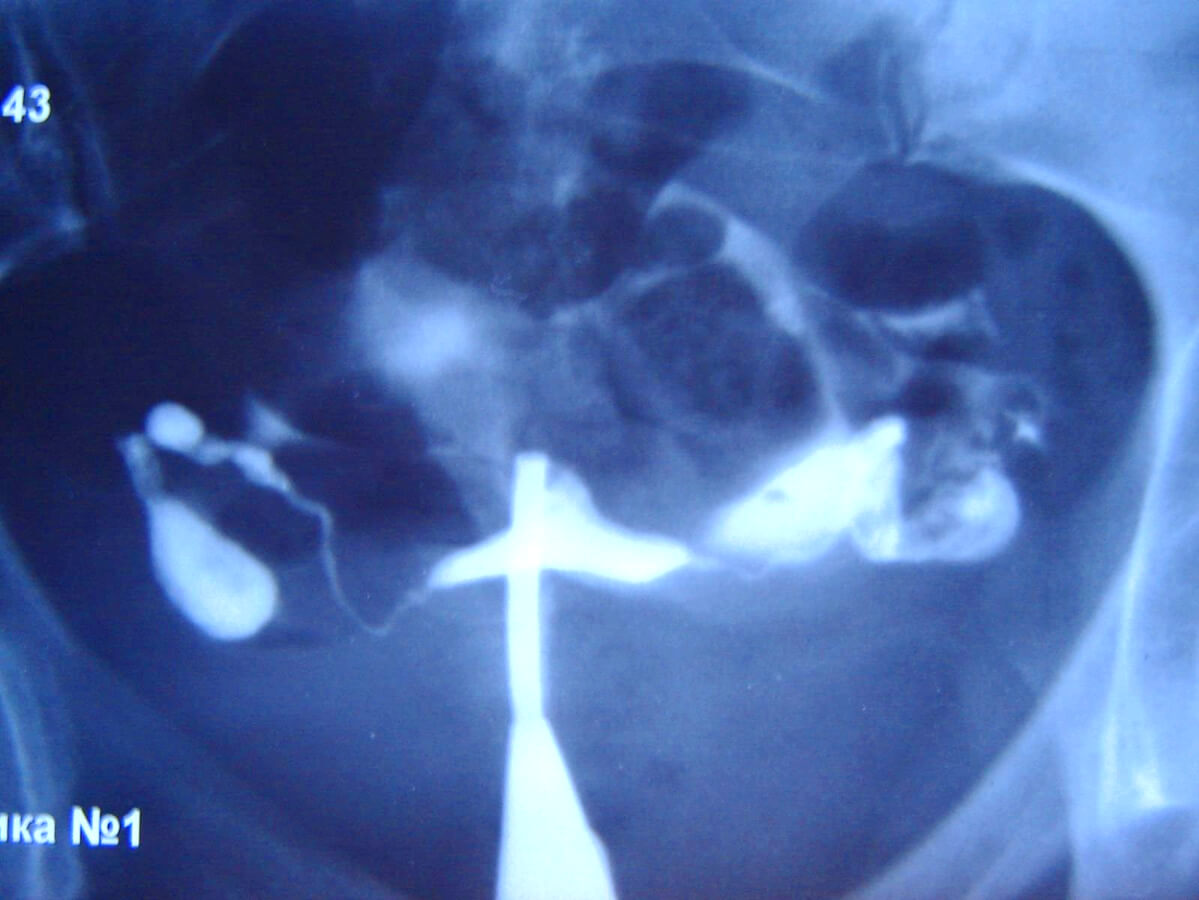

Медицинские снимки: Проходимость маточных труб